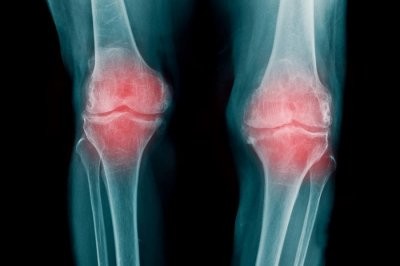

Названы богатые полифенолами продукты, которые помогут при лечении ревматоидного артрита

Ревматоидный артрит полностью не излечиваются. Порой даже временного облегчения добиться трудно. А между тем ревматоидный артрит, помимо сильной и постоянной боли, может привести к таким серьезным заболеваниям, как эрозия кости, деформация суставов. Может даже обездвижить.